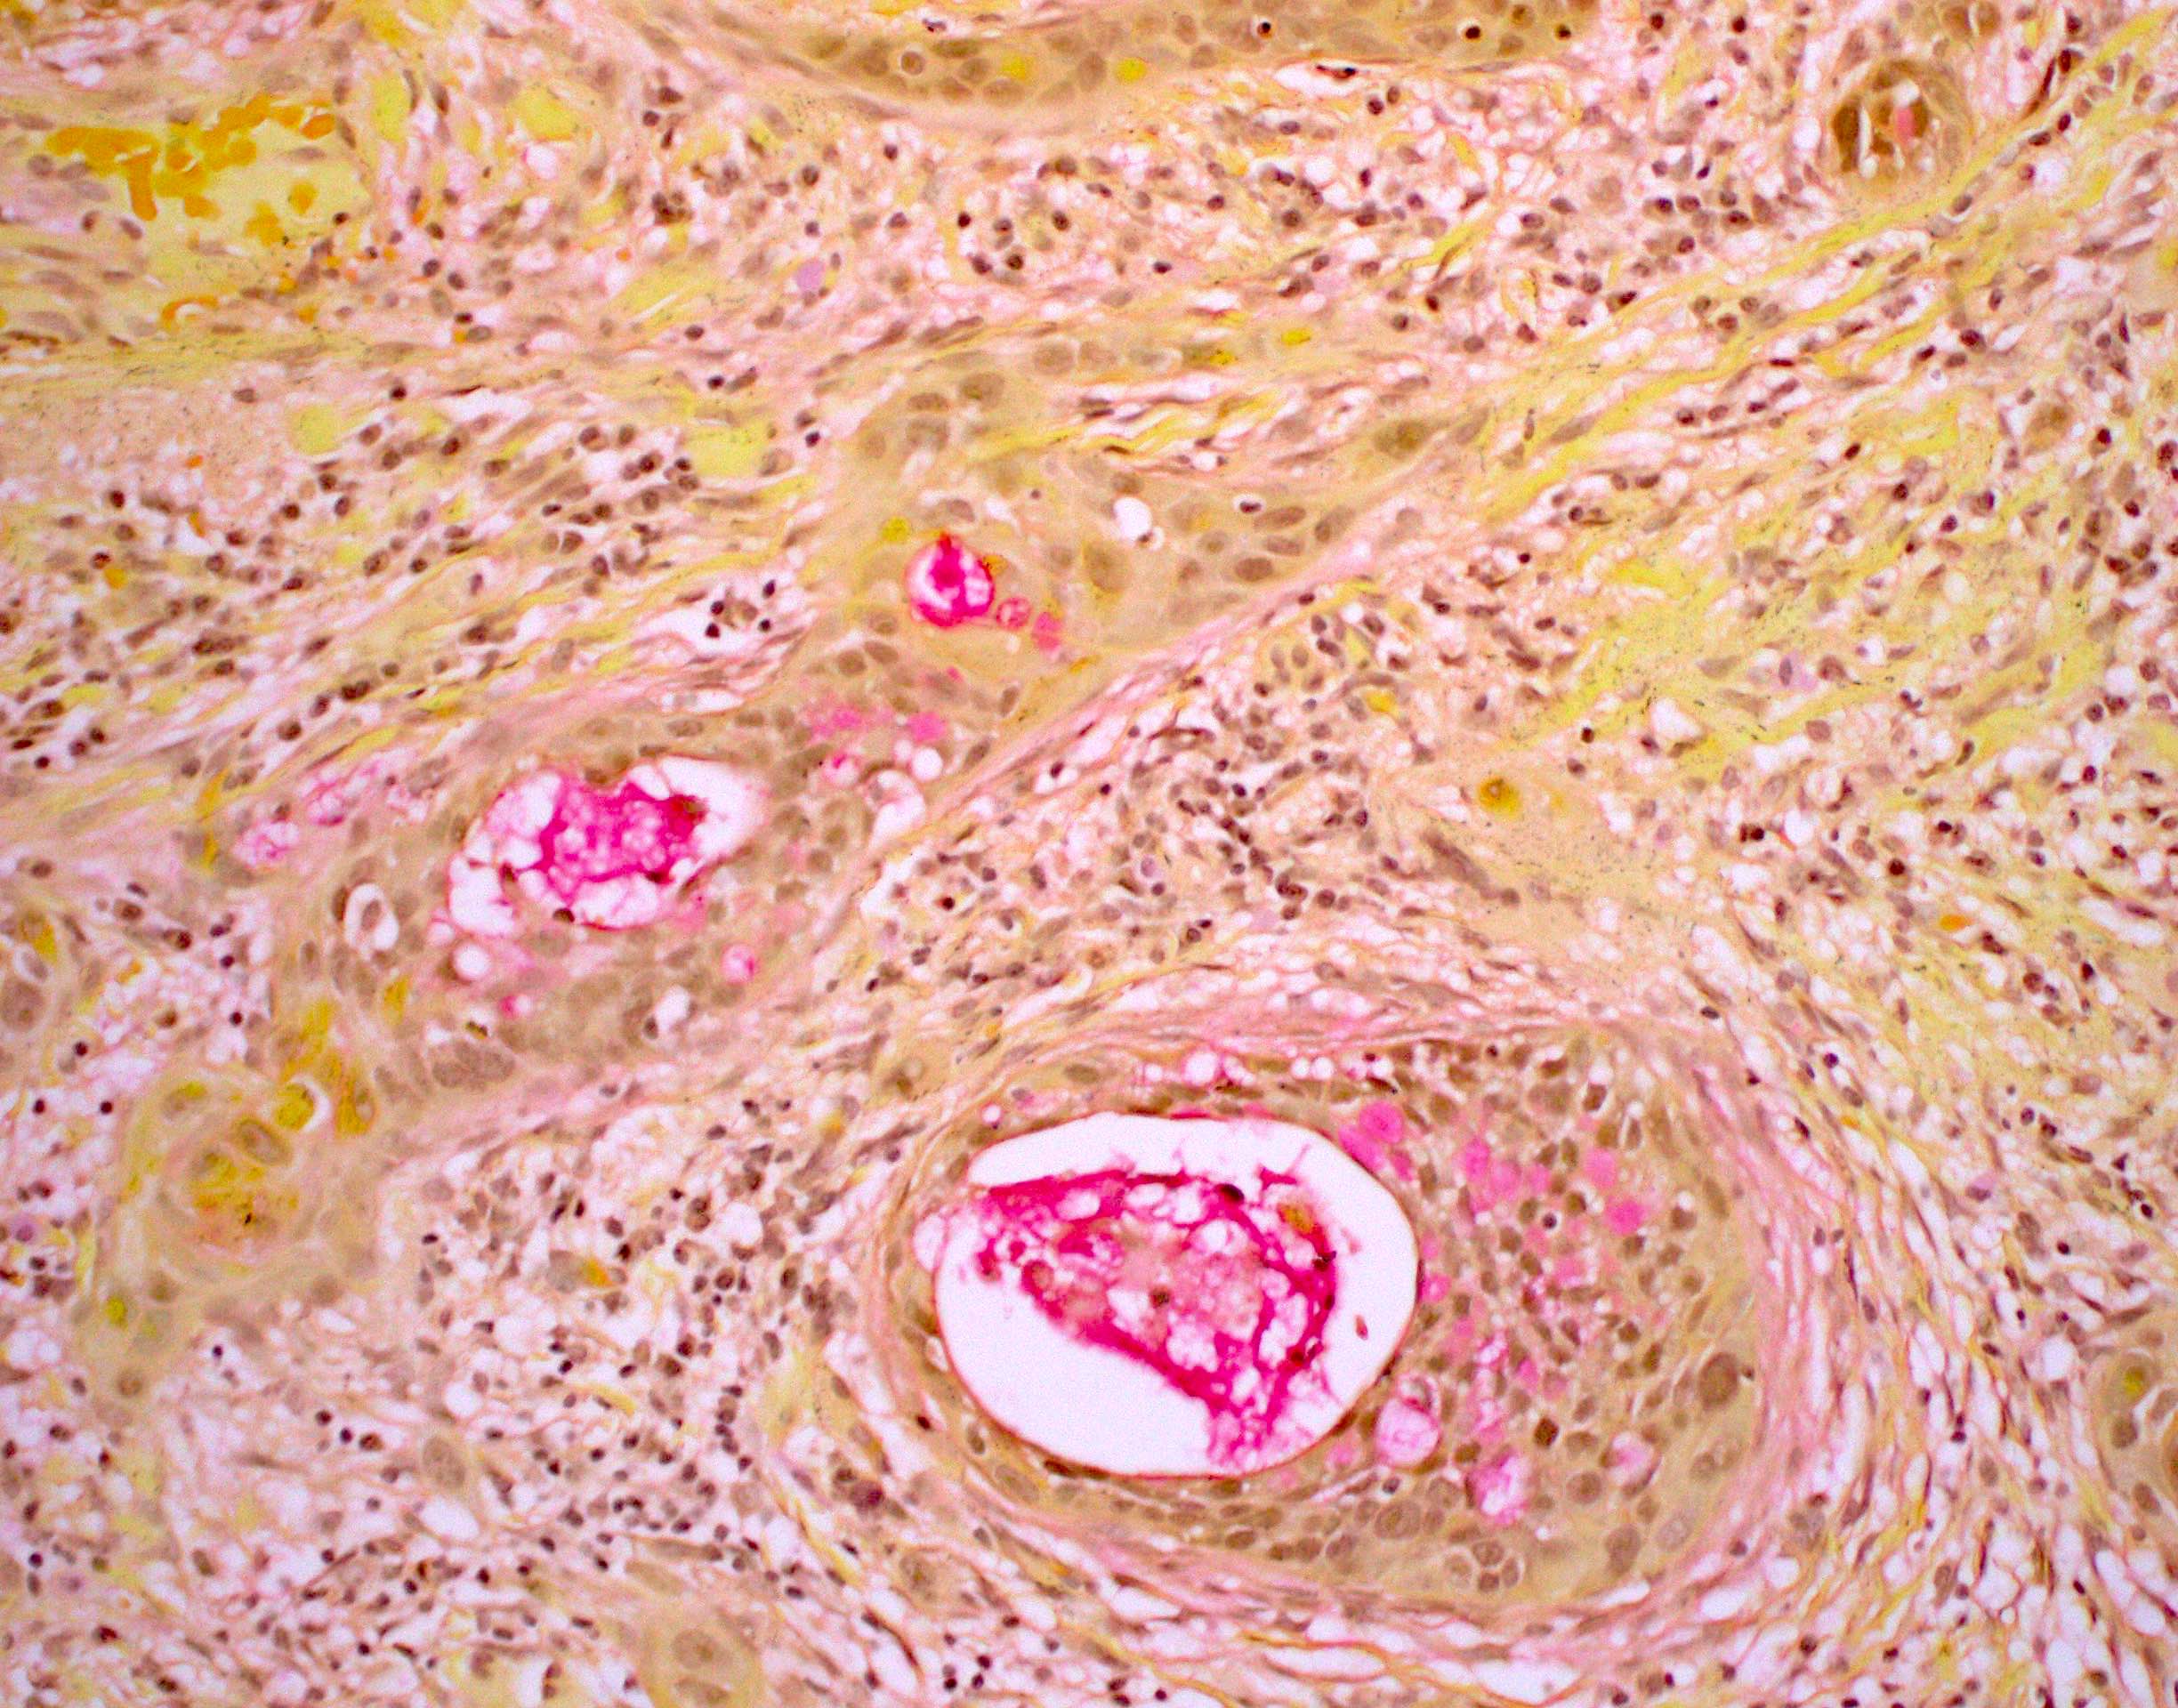

- Spindle cell / sarcomatoid squamous cell carcinoma (Am J Otolaryngol 2008;29:123)

- Most commonly occurs postradiotherapy or as second primary

- Mesenchymal in appearance

- Atypical plump spindled cells arranged in fascicles or storiform pattern

- May have metaplastic or neoplastic cartilage or bone

Microscopic (histologic) images

Contributed by Ruta Gupta, M.B.B.S., M.D.